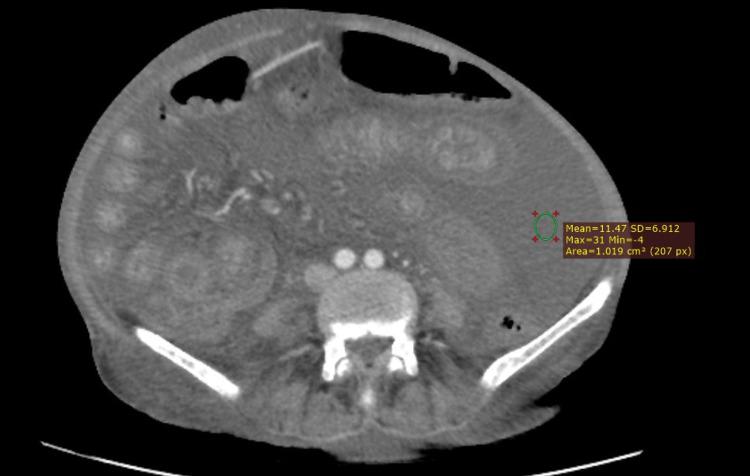

Objective The goal of this research was to define the diagnostic precision of CT signs to distinguish malignant ascites from cirrhotic ascites. Ascitic fluid cytology was kept as the gold standard. Study design This research was a prospective cross-sectional study. Place and duration of the study Participants' recruitment started on July 15, 2021, and the whole study lasted about three months till October 15, 2021, at the Radiology Department of Pakistan Institute of Medical Sciences, Islamabad. Patients and methods A total of 80 patients were included in the research and divided into two groups grounded on the cirrhotic or malignant etiology of the ascites based on their fluid cytology. Ascites volume, relative spread between the lesser sac and greater peritoneal cavity, the wall thickness of gallbladder, density of ascites, parietal peritoneum thickness and degree of its enhancement, and presence of septa and loculations were some of the major CT signs studied. Results The average age of patients included in this study was 36.2 ± 6.67 years (range 29-49 years). Of the 80 patients, 50 (62.5 %) were men, and 30 (37.5 %) were women. CT signs associated with the malignant ascites reported in this study were fluid present in the lesser sac (p = 0.03), peritoneal thickening and degree of its enhancement (p = 0.05), increased ascites density (p= 0.001), and presence of septa and loculations (63.6 % of malignant ascites). However, gallbladder wall thickness did not show any variation between both groups. Conclusion We conclude that in the diagnosis of malignant ascites, CT scan imaging can play a vital role. This research approves and testifies the benefits of indirect signs such as the spread of ascites, increased density of ascites, thickening and enhancement of parietal peritoneum, and ascitic fluid complexity in pointing out malignancy as a cause of ascites.

摘要

目的 本研究的目的是确定CT征象对鉴别恶性腹水和肝硬化腹水的诊断准确性。腹水细胞学检查作为金标准。

患者和方法 本研究共纳入80例患者,根据腹水的细胞学检查结果,基于肝硬化或恶性病因将其分为两组。研究的主要CT征象包括腹水容量、小网膜囊与大腹膜腔之间的相对扩散、胆囊壁厚度、腹水密度、壁层腹膜厚度及其强化程度,以及隔和分隔的存在情况。

结果 本研究纳入患者的平均年龄为36.2±6.67岁(范围29 - 49岁)。80例患者中,50例(62.5%)为男性,30例(37.5%)为女性。本研究报道的与恶性腹水相关的CT征象有小网膜囊内有液体(p = 0.03)、腹膜增厚及其强化程度(p = 0.05)、腹水密度增加(p = 0.001)以及隔和分隔的存在(恶性腹水中63.6%)。然而,两组之间胆囊壁厚度无差异。

结论 我们得出结论,在恶性腹水的诊断中,CT扫描成像可发挥重要作用。本研究证实并验证了间接征象如腹水扩散、腹水密度增加、壁层腹膜增厚和强化以及腹水复杂性在指出恶性肿瘤为腹水病因方面的益处。